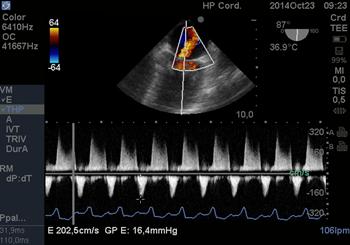

El eje corto transgástrico basal 0° nos permite una visión del orificio anatómico para realizar la planimetría directa de la válvula. (Figura 20) Este método permite realizar mediciones en pacientes con fibrilación auricular y lesiones regurgitantes asociadas. Cuando el área es < o = de 1.5cm2 la estenosis se considera severa(33).

Figura 20 imagen transgástrica a 0° medición por planimetría de VM , estenosis severa (menor a 1cm2)

Luego de valorar el daño valvular en 2D,utilizamos el Doppler para estudiar los gradientes transvalvulares máximos(34). Usando la ecuación de Bernoulli es posible determinar los gradientes transvalvulares como una medida de la severidad de la lesión. El gradiente de presión diastólica se mide con Doppler Continuo el “gradiente medio” es el que mejor expresa la gravedad de la enfermedad: leve < de 5mmHg, medio de 5 a 10 severo gradiente medio >de 10mmHg.

La cuantificación del área valvular se realiza por planimetría directa o por el Tiempo de Hemipresión(THP). Este método desarrollado por la Dra. Hatle , establece que el tiempo de caída de la presión diastólica pico a la mitad de su valor inicial, está inversamente relacionado con el área valvular mitral (AVM) :

AVM=220/THP (donde 220 es una constante empírica).(35)(36)

El tiempo de hemipresión (THP), (Figura 21) también está relacionado con el gradiente inicial y la compliance ventricular. Su medición es confiable, sencilla y rápida.

Figura 22 con Doppler Continuo medición y cálculo del área mitral a través del tiempo de hemipresión. Estenosis severa.